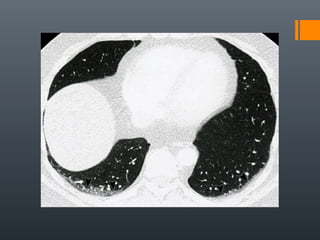

O documento discute vários conceitos radiológicos incluindo consolidação, atelectasia, nódulos, pseudocavidades e padrões intersticiais, fornecendo definições, sinais e diagnósticos diferenciais para cada tópico. Ele também discute a redução da atenuação pulmonar e fornece um link para mais informações.